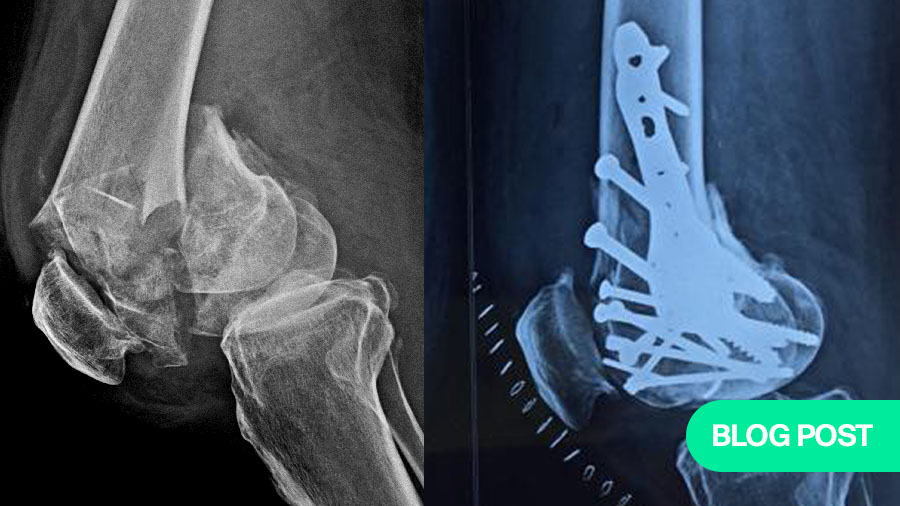

A 58-year-old farmer, the patient had always been physically active despite some age-related degenerative changes in his knees. His injury occurred from a fall in which he landed directly on his knee, resulting in a highly comminuted fracture. On initial inspection, the fracture resembled a shattered stone, with seven to eight individual fragments within the knee joint. These fragments included articular surfaces critical for knee function, making the restoration of joint congruity both urgent and exceptionally challenging.

The complexity of the injury required a structured, multi-step approach, starting with comprehensive imaging. While X-rays provided an initial overview, it was the CT scan that delivered the critical 3D visualization of the fracture pattern. This enabled precise identification of each fragment and helped enormously in preoperative planning.

The joint was exposed via an open procedure similar to that used in total knee arthroplasty, allowing us full visibility. What we encountered were multiple fragments, many of which were too small to individually identify without proper sequencing – much like solving a jigsaw puzzle. The first step was to reconstruct the articular surface using temporary fixation with Kirschner wires (K-wires). Fragment by fragment, we identified and aligned them to reform the joint’s surface. Once reconstructed, this block of bone was then aligned with the diaphysis of the tibia.

Permanent fixation was then achieved using two plates and multiple screws. Due to the unavailability of a dedicated plate for this particular fracture configuration, we used a shoulder locking plate, which fitted anatomically well for medial and lateral support. This unorthodox but carefully considered decision underscores the importance of improvisation when conventional tools fall short.